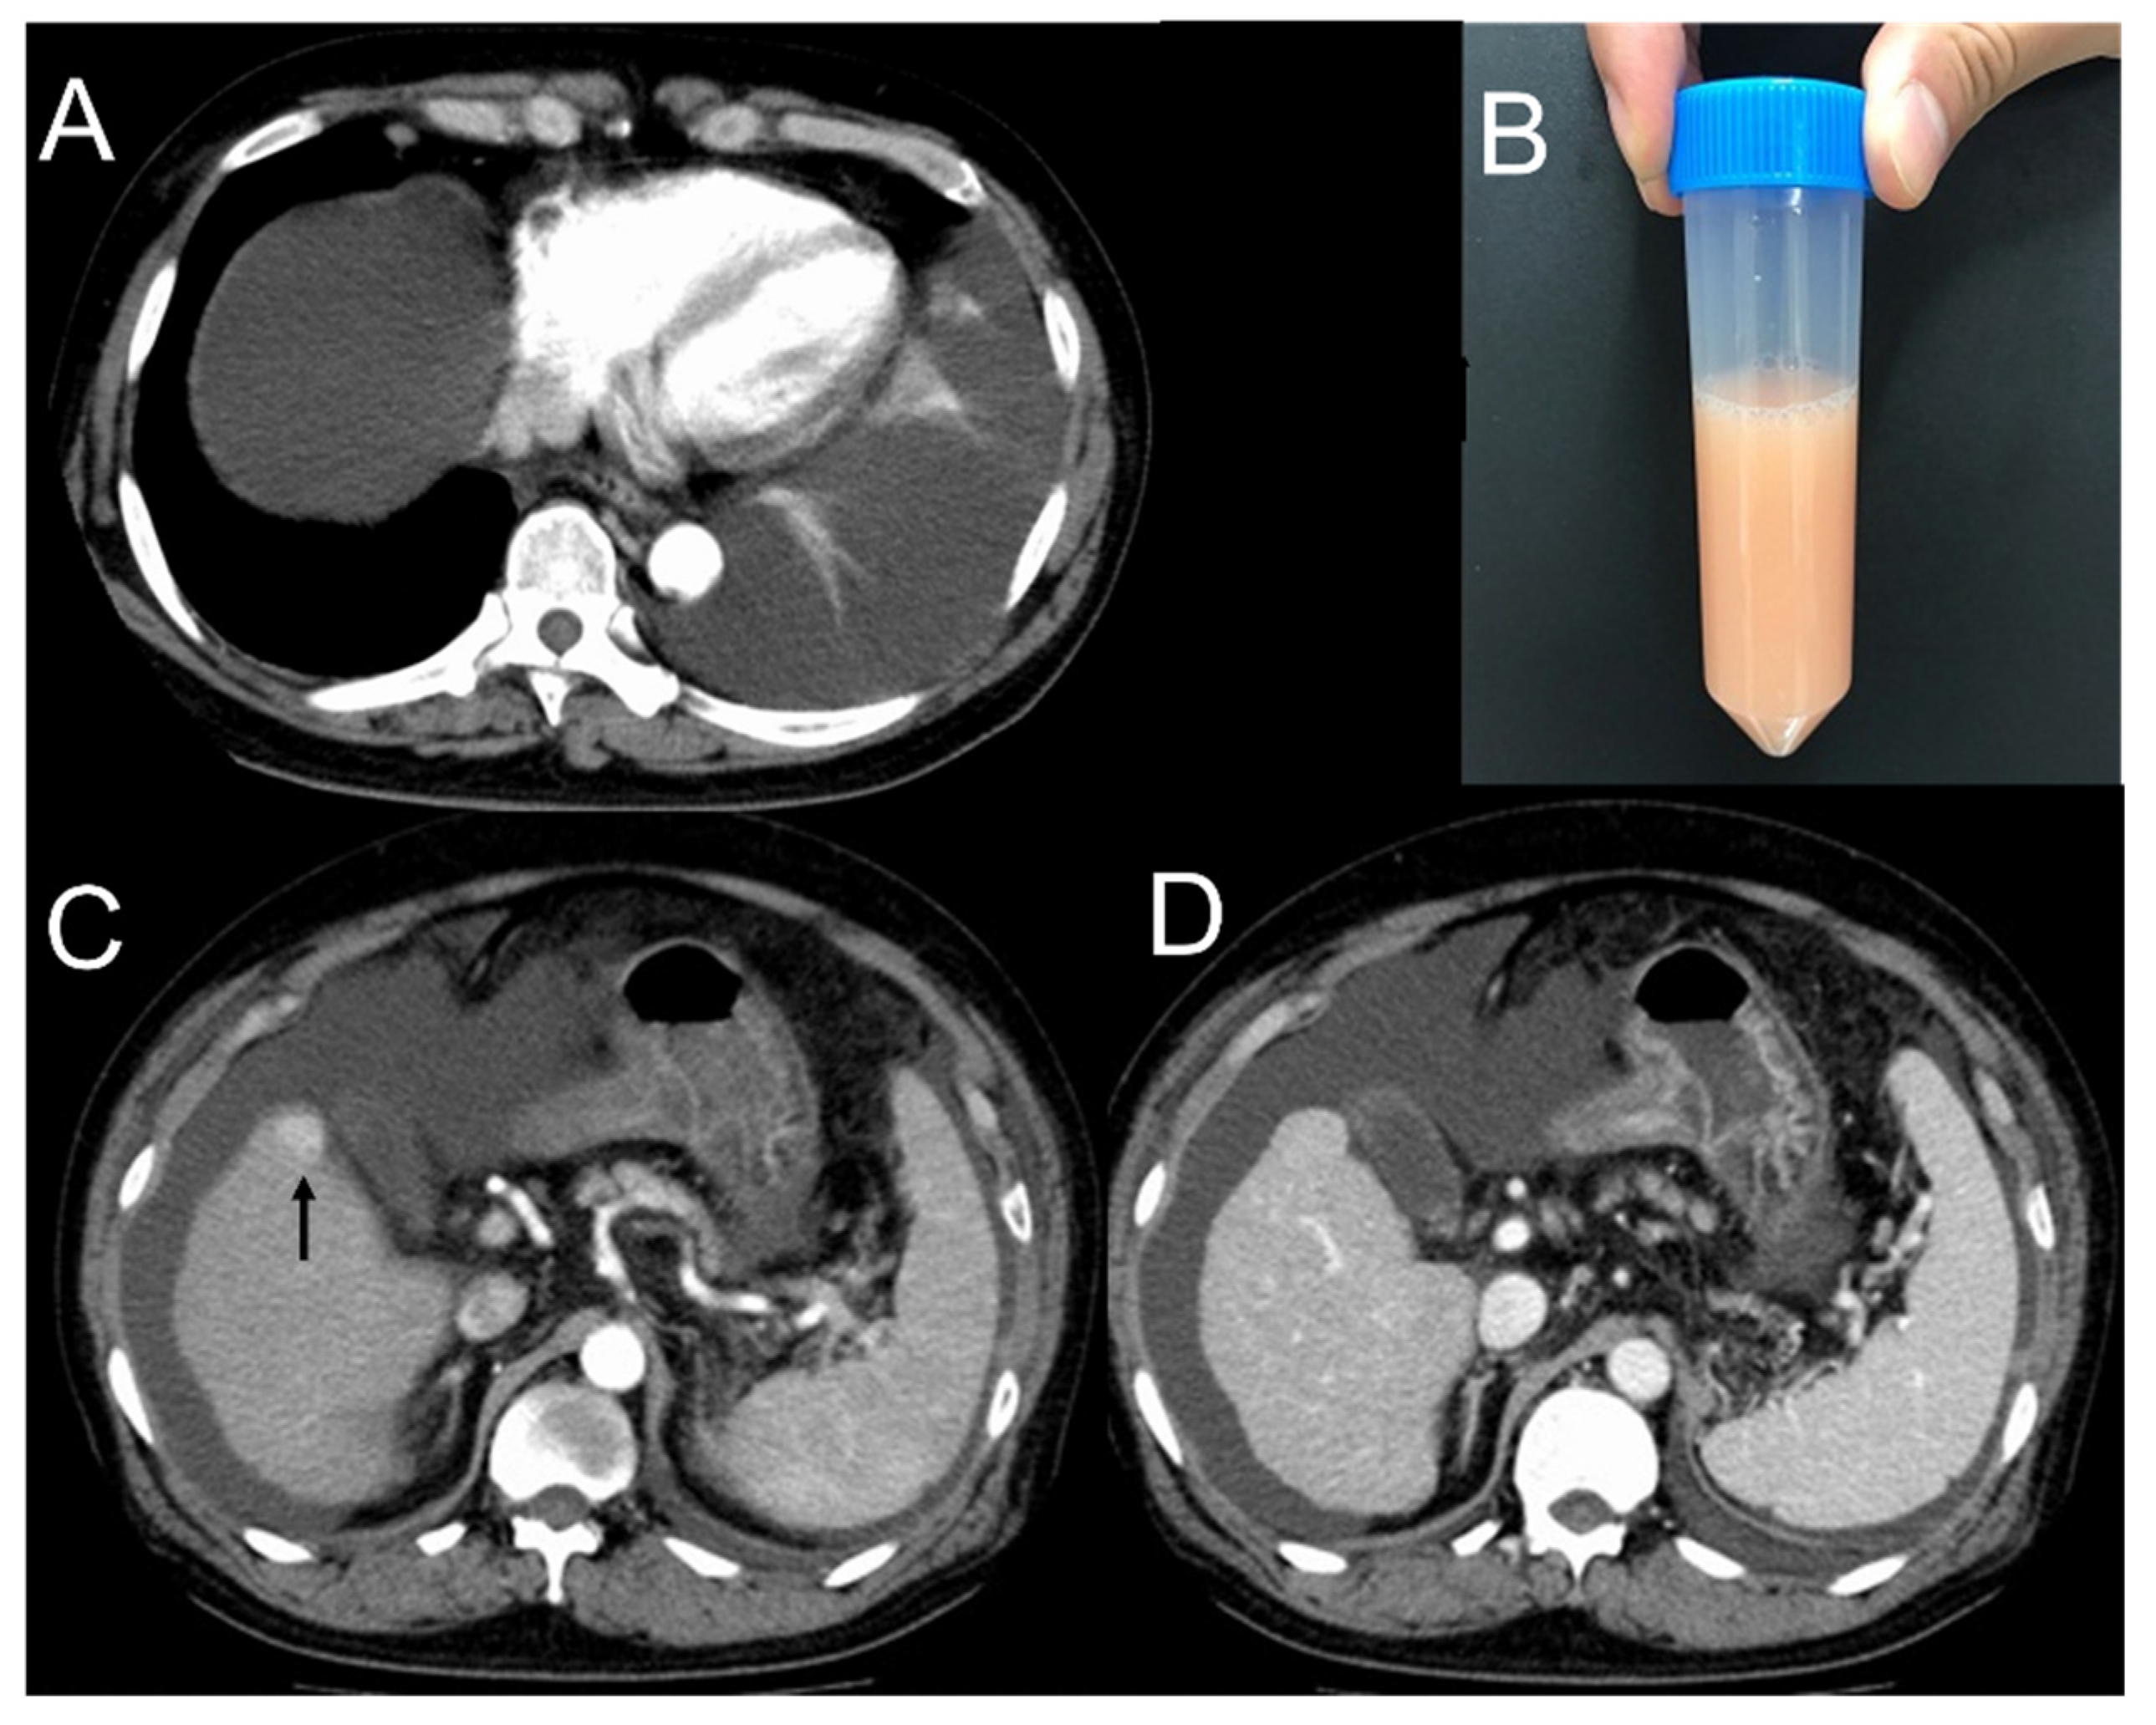

2. Case Presentation